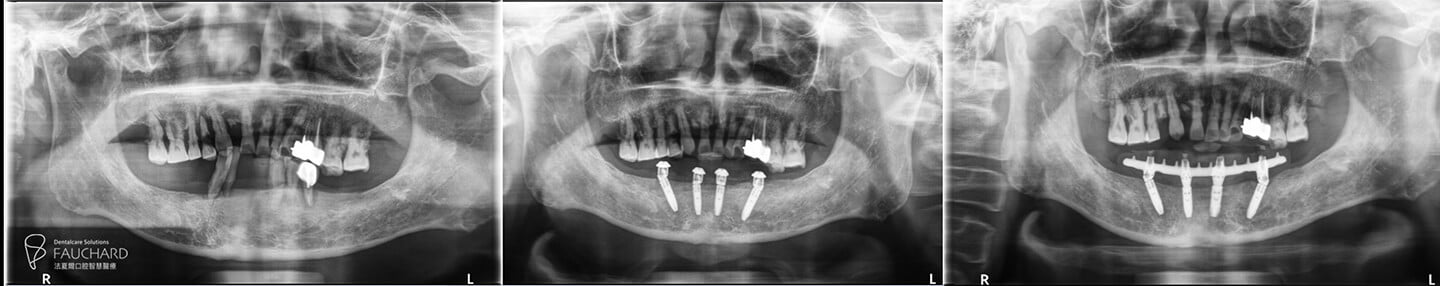

下顎 All-on-4 全口重建術前術後對比